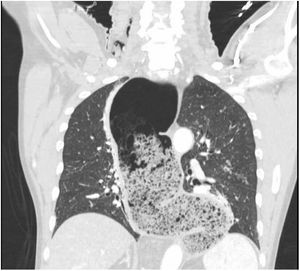

A 61-year-old man with a history of achalasia treated in 2015 with fundoplication, without other known conditions, presents to the ER with sudden dyspnea and acute hypoxemic respiratory failure. On physical examination, leftward tracheal deviation with cervical edema and subcutaneous tissue crepitus is observed (Fig. 1). Once stabilized with endotracheal intubation and connected to invasive mechanical ventilation, suspicion of esophageal disease leads to a contrast-enhanced thoracic CT scan that confirms the presence of a 7 cm megaesophagus (AP axis) with fluid and air levels inside (Fig. 2), and bubbles of pneumomediastinum with extensive cervical subcutaneous emphysema (Fig. 3), which are consistent with cervical esophageal perforation. Definitive treatment: esophagectomy.